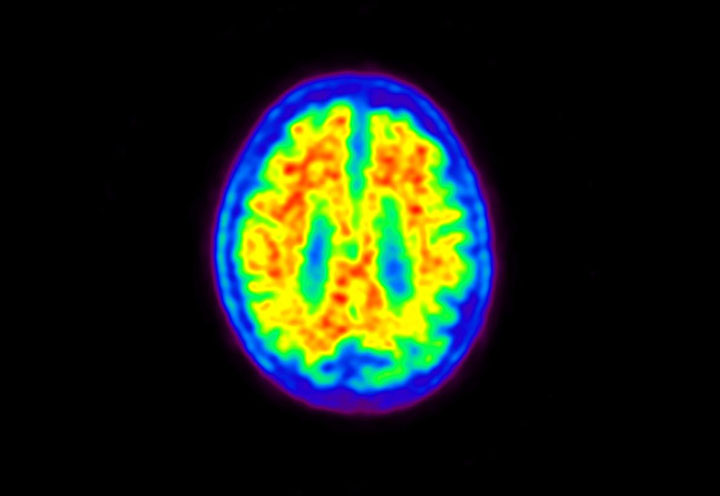

Head / Case5 : Amyloid

Axial

Courtesy : Kindai University Hospital

- Imaging protocol

- Injected dose: 4.27 MBq/kg, 18F-Flutemetamol

- Uptake time: 99 minutes

- Scan time: 20 minutes